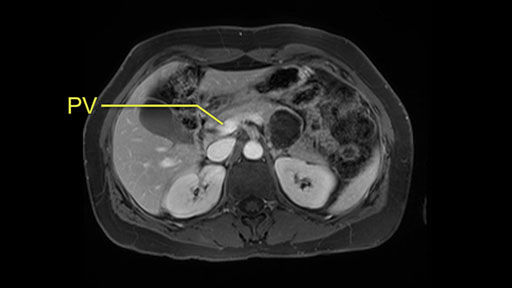

The slowing down moments or considerations that I give when I look at the scan and plan my distal pancreatectomy is how far away the tumor is to the portal vein and do I have to formally create a tunnel behind the pancreas on top of the portal vein or do I have to take the pancreas further to the left of the portal vein or the patient’s left of the portal vein. So here I can see that here is the tumor here. I can see that the tumor is a fair way away to the patient’s right and so I will likely not have to take or create the tunnel formally in this procedure. And that speaks a lot to the resection margins. So its important when you’re doing a distal pancreatectomy or any procedure potentially for oncologic reasons to get clearance of the tumor and to take the tumor kind of intact.

I mentioned earlier that transection at the neck is the area that I would normally do as long as I have good margin from the lesion. And if the margin is not enough, I would go further to go to the right of the PV-SMV area at the junction and do the transection at that point.

Proximity of lesion to PV-SMV

Key features that I look at the imaging are: first I look at the distance between the cyst and the portal vein SMV confluence. So there are guidelines for this, they call the Yonsei guidelines, to decide to do it laparoscopically or open and basically it says that if it’s a cancer, at least a centimeter away from the celiac trunk or the venous confluence. This is a cyst. So maybe you could stretch that a bit, but you don't want to get into trouble there. So for this cyst if you look at it, it's nicely away from the confluence.

So unfortunately I cannot show you a coronal view but you can see it easily on this scan, going down first you see the celiac trunk and you see here, quite a nice distance between the celiac trunk and the beginning of the mucinous cyst. And if you go up here and follow down the portal vein confluence you also see a nice distance there.